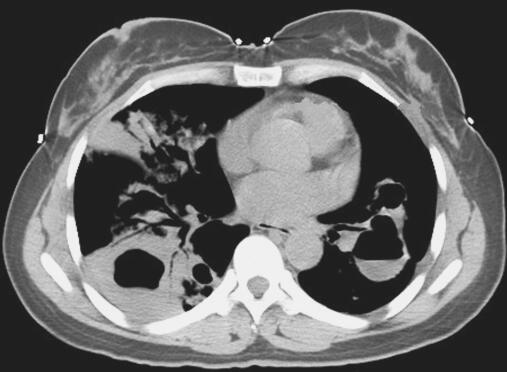

患者入院后考虑肺囊肿继发感染,给予抗感染治疗,完善相关检查,血常规:WBC 11.19×109/L,N% 68.90%;肺肿瘤标志物:CEA 2.46ng/ml,CYFRA 4.34ng/ml,NSE 9.38ng/ml;胸部CT示双肺气液囊肿并感染可能(图1);绒毛膜促性腺激素(β)HCG-BETA 5.48mIU/ml;电子支气管镜镜检未见异常;电子支气管镜肺活检病理示:子宫胎盘部位滋养细胞肿瘤肺转移。

图1 肺CT示双肺气液囊肿并感染可能

此例患者胸部CT提示双侧肺野多发液气囊性改变,考虑与滋养细胞在肺内破坏血管壁进入肺泡,使周围组织发生炎性浸润、出血、水肿,各肺泡病变融合成团,中心坏死,形成囊肿样改变,同时滋养细胞进入呼吸性细支气管为中心的细支气管周围组织发生炎性浸润,使呼吸性细支气管狭窄、闭塞,当囊肿内黏液潴留过多,或继发化脓性感染时,囊腔易与呼吸性细支气管穿透,形成单向性活瓣样通气,从而导致囊腔内压力不断升高,形成张力性液气囊肿改变。